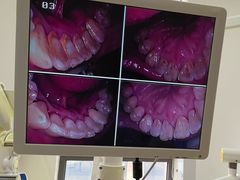

• 圣贝口腔(海淀店)

• -圣贝口腔(海淀店)

牛油果酱空心菜 | 24-07-17